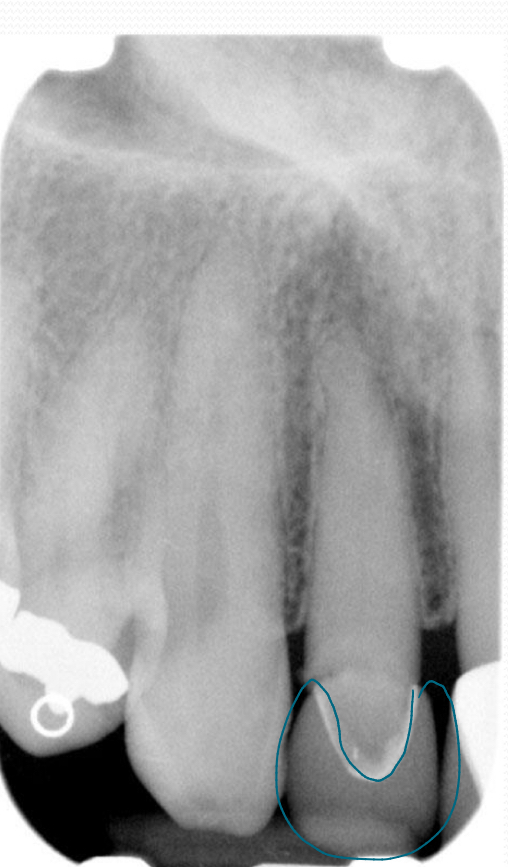

All porcelain restorations:

Resembles radiopacity of dentin